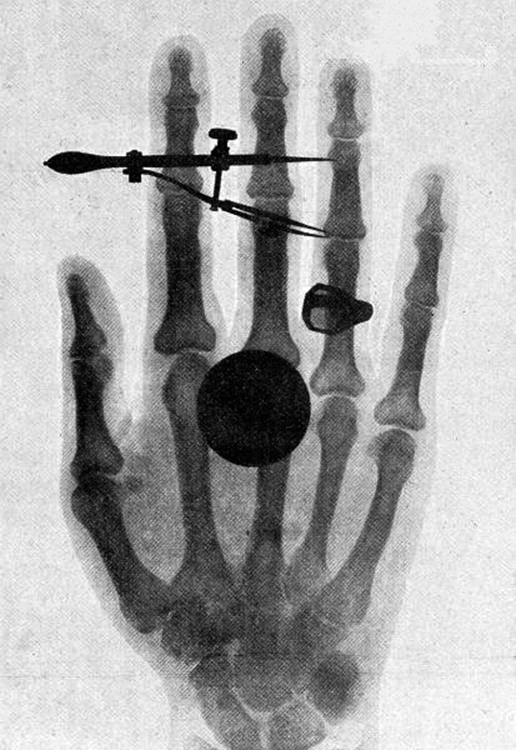

index-1041_1.jpg

index-1041_2.jpg

Figure 29.12 One of the first x-ray images, taken by Röentgen himself. The hand belongs to Bertha Röentgen, his wife. (credit: Wilhelm Conrad Röntgen, via Wikimedia

Commons)

High photon energy also enables γ rays to penetrate materials, since a collision with a single atom or molecule is unlikely to absorb all the γ ray’s

energy. This can make γ rays useful as a probe, and they are sometimes used in medical imaging. x rays, as you can see in Figure 29.11, overlap with the low-frequency end of the γ ray range. Since x rays have energies of keV and up, individual x-ray photons also can produce large amounts

of ionization. At lower photon energies, x rays are not as penetrating as γ rays and are slightly less hazardous. X rays are ideal for medical imaging,

their most common use, and a fact that was recognized immediately upon their discovery in 1895 by the German physicist W. C. Roentgen

(1845–1923). (See Figure 29.12.) Within one year of their discovery, x rays (for a time called Roentgen rays) were used for medical diagnostics.

Roentgen received the 1901 Nobel Prize for the discovery of x rays.